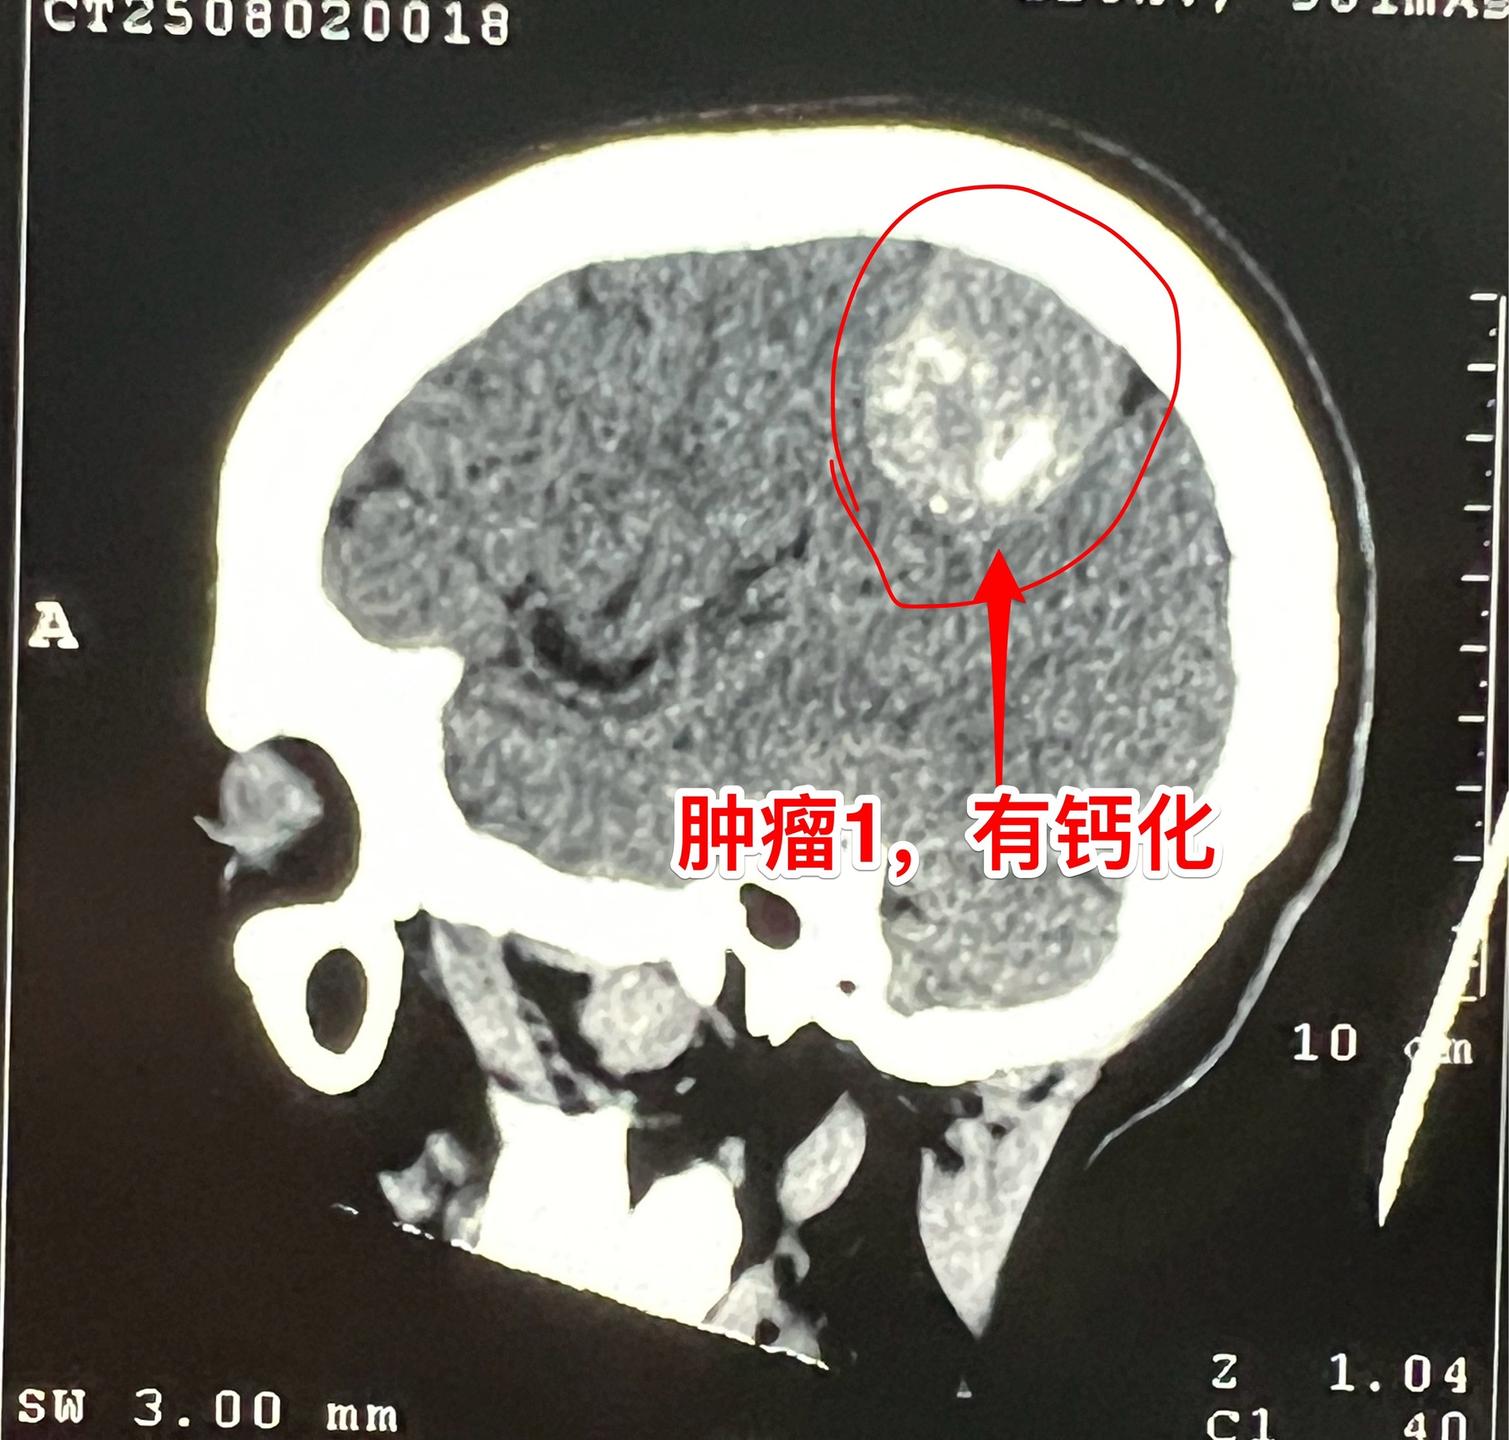

因头痛检查发现脑部有三个瘤。56岁女性,黄梅县人。平时身体很好,因路滑...